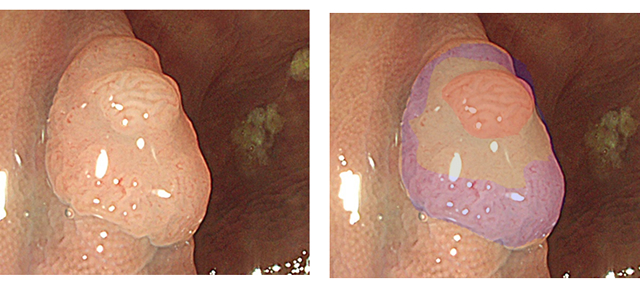

下の写真は内視鏡医なら、表面に「不整」があることから「High Risk腺腫」と診断しますが、病理は「Low Risk腺腫」でした。このような食い違いは、時に経験されますが、分子生物学的に考察するなら以下のようになります。

内視鏡医が昔から観ていた「不整」とは腫瘍進化(Intra Tumor Heterogenity)=「ゲノムの不安定性」であり、病理医の観ていた「異型度」というのは細胞核の形態異常=細胞分裂時のM期check pointの異常による染色体異常(CIN)に相当します。大腸癌の8割は染色体異常(CIN)を伴うのですが、必ずしも病理学的異型度は遺伝子変異の悪性度とは完全に対応しません。下のような病変は染色体異常が軽いため、「核の異型度」が軽いと思われます。

詰まる所、ポリープの危険性を正確に評価することは(全ゲノム解読以外では)、難しい訳です。(個人的には内視鏡所見が病理診断より優先されると考えますが。)